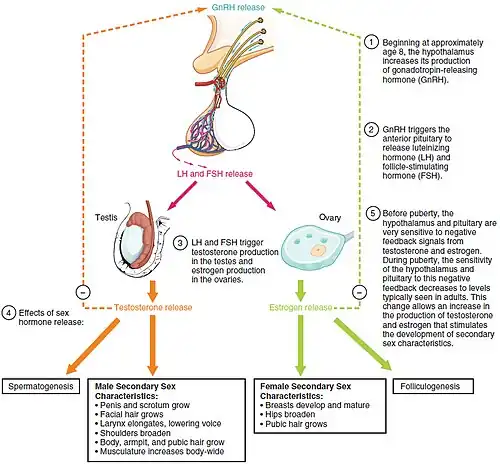

Kisspeptins (including kisspeptin-54 (KP-54), formerly known as metastin) are proteins encoded by the KISS1 gene in humans. Kisspeptins are ligands of the G-protein coupled receptor, GPR54.[5] Kiss1 was originally identified as a human metastasis suppressor gene that has the ability to suppress melanoma and breast cancer metastasis.[6] Kisspeptin-GPR54 signaling has an important role in initiating secretion of gonadotropin-releasing hormone (GnRH) at puberty, the extent of which is an area of ongoing research.[7] Gonadotropin-releasing hormone is released from the hypothalamus to act on the anterior pituitary triggering the release of luteinizing hormone (LH), and follicle stimulating hormone (FSH). These gonadotropic hormones lead to sexual maturation and gametogenesis. Disrupting GPR54 signaling can cause hypogonadotrophic hypogonadism in rodents and humans. The Kiss1 gene is located on chromosome 1. It is transcribed in the brain, adrenal gland, liver, gonads, and pancreas.

Kisspeptin was found to play a role in hypogonadotropic hypogonadism in 2003, which was supported by several independent lab groups.[11] A mutation in GPR54 was considered responsible for this abnormality because those who held this mutation, or were missing GPR54 altogether, had problems in gonadal development during puberty.[11] Several other phenotypes related to this mutation included a smaller sex steroid and gonadotropin concentration in the circulating blood and even sterility.[11] These observations prompted the research on how kisspeptin is involved during the beginning of puberty. This research led to the discovery that kisspeptin stimulates the neurons that were involved in the release of gonadotropin-releasing hormone (GnRH) and possibly may have some impact on the release of luteinizing hormone (LH) and follicle-stimulating hormone (FSH).[11]

The onset of puberty is marked by an increase in gonadotropin secretion, which leads to sexual maturity and the ability to reproduce. Puberty can also be affected by a range of environmental factors, and is known to be affected by a person's metabolic capacity.[20] Gonadotropin secretion is brought about and regulated by gonadotropin releasing hormone (GnRH). GnRH leads to the release of luteinizing hormone (LH) and follicle stimulating hormone (FSH), which primarily target the gonads to trigger puberty and reproduction. The primary event that leads to the beginning of puberty is the activation of GnRH neurons. This event is thought to involve kisspeptin/GPR54 signaling, which leads to the eventual activation of GnRH neurons.[17] Several studies have confirmed that addition of kisspeptin to biological systems including rat, mouse, and sheep are able to bring about the release of LH and FSH.

Kisspeptin's ability to stimulate the release of GnRH and gonadotropins is the result of its effect on GnRH release at the hypothalamus. In rat hypothalamus, it was found that over three-fourths of GnRH neurons coexpress the receptor for kisspeptin, GPR54, in their RNA. Kisspeptin was also able to bring about the release of GnRH both ex vivo and in vivo in rat and sheep. It can be concluded that by activating GnRH neurons in the hypothalamus, kisspeptin causes GnRH release which leads to the release of FSH and LH.[20] The major role kisspeptin/GPR54 plays in sexual development was initially found in sexually immature humans and mice who had mutations that blocked the expression of the GPR54 gene. In rats, the initiation of puberty accompanied a greater presence of KISS1 and GPR54 in mRNA. The same events were later observed in mammals, where KISS1 and GPR54 mRNA increased more than twofold in the hypothalamus. This suggests that there is greater expression of KISS1 and potentially even GPR54 at the onset of puberty leading to an increase in kisspeptin/GPR54 signaling that results in the activation of the gonadotropin pathway.[20] The addition of kisspeptin to female rats who had yet to mature led to the initiation of gonadotropin pathway. In humans, it was shown that females at the beginning stages of puberty had much higher kisspeptin levels than those females of the same age who had yet to begin puberty. It has been concluded that the activation of the GPR54/kisspeptin pathway is a catalyst that leads to puberty onset.[20]